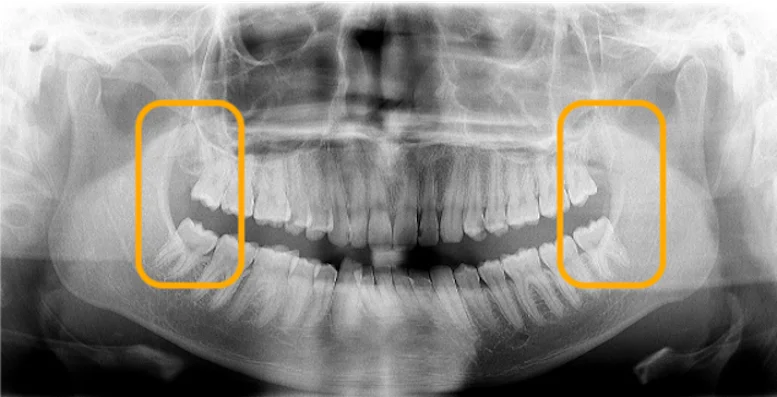

2.歯並びに悪影響が出ている

親知らずはこのように横向きに生えることが多いです。 横向きに生えた親知らずは手前の歯をグイグイと押し、歯並びに悪影響を与えることがあります。

先ほどご説明した通り、親知らずが正常に生えて機能している場合には放置していても問題ありません。 横向きに生えていたり埋まっている親知らずを放置した場合はどうなるのか。 その場合、「親知らずを抜いた方がいいケース」でご紹介したような状態になる可能性があります。

• 歯並びが悪くなる

• 手前の歯を溶かしてしまう